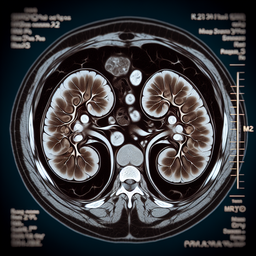

МРТ наднирників

Магнітно-резонансна томографія (МРТ) наднирників — це неінвазивне дослідження, яке використовує магнітні поля і радіохвилі для отримання детальних зображень наднирників і навколишніх тканин. Ця процедура допомагає лікарям виявити аномалії, пухлини або інші стани, які можуть впливати на функціонування наднирників.